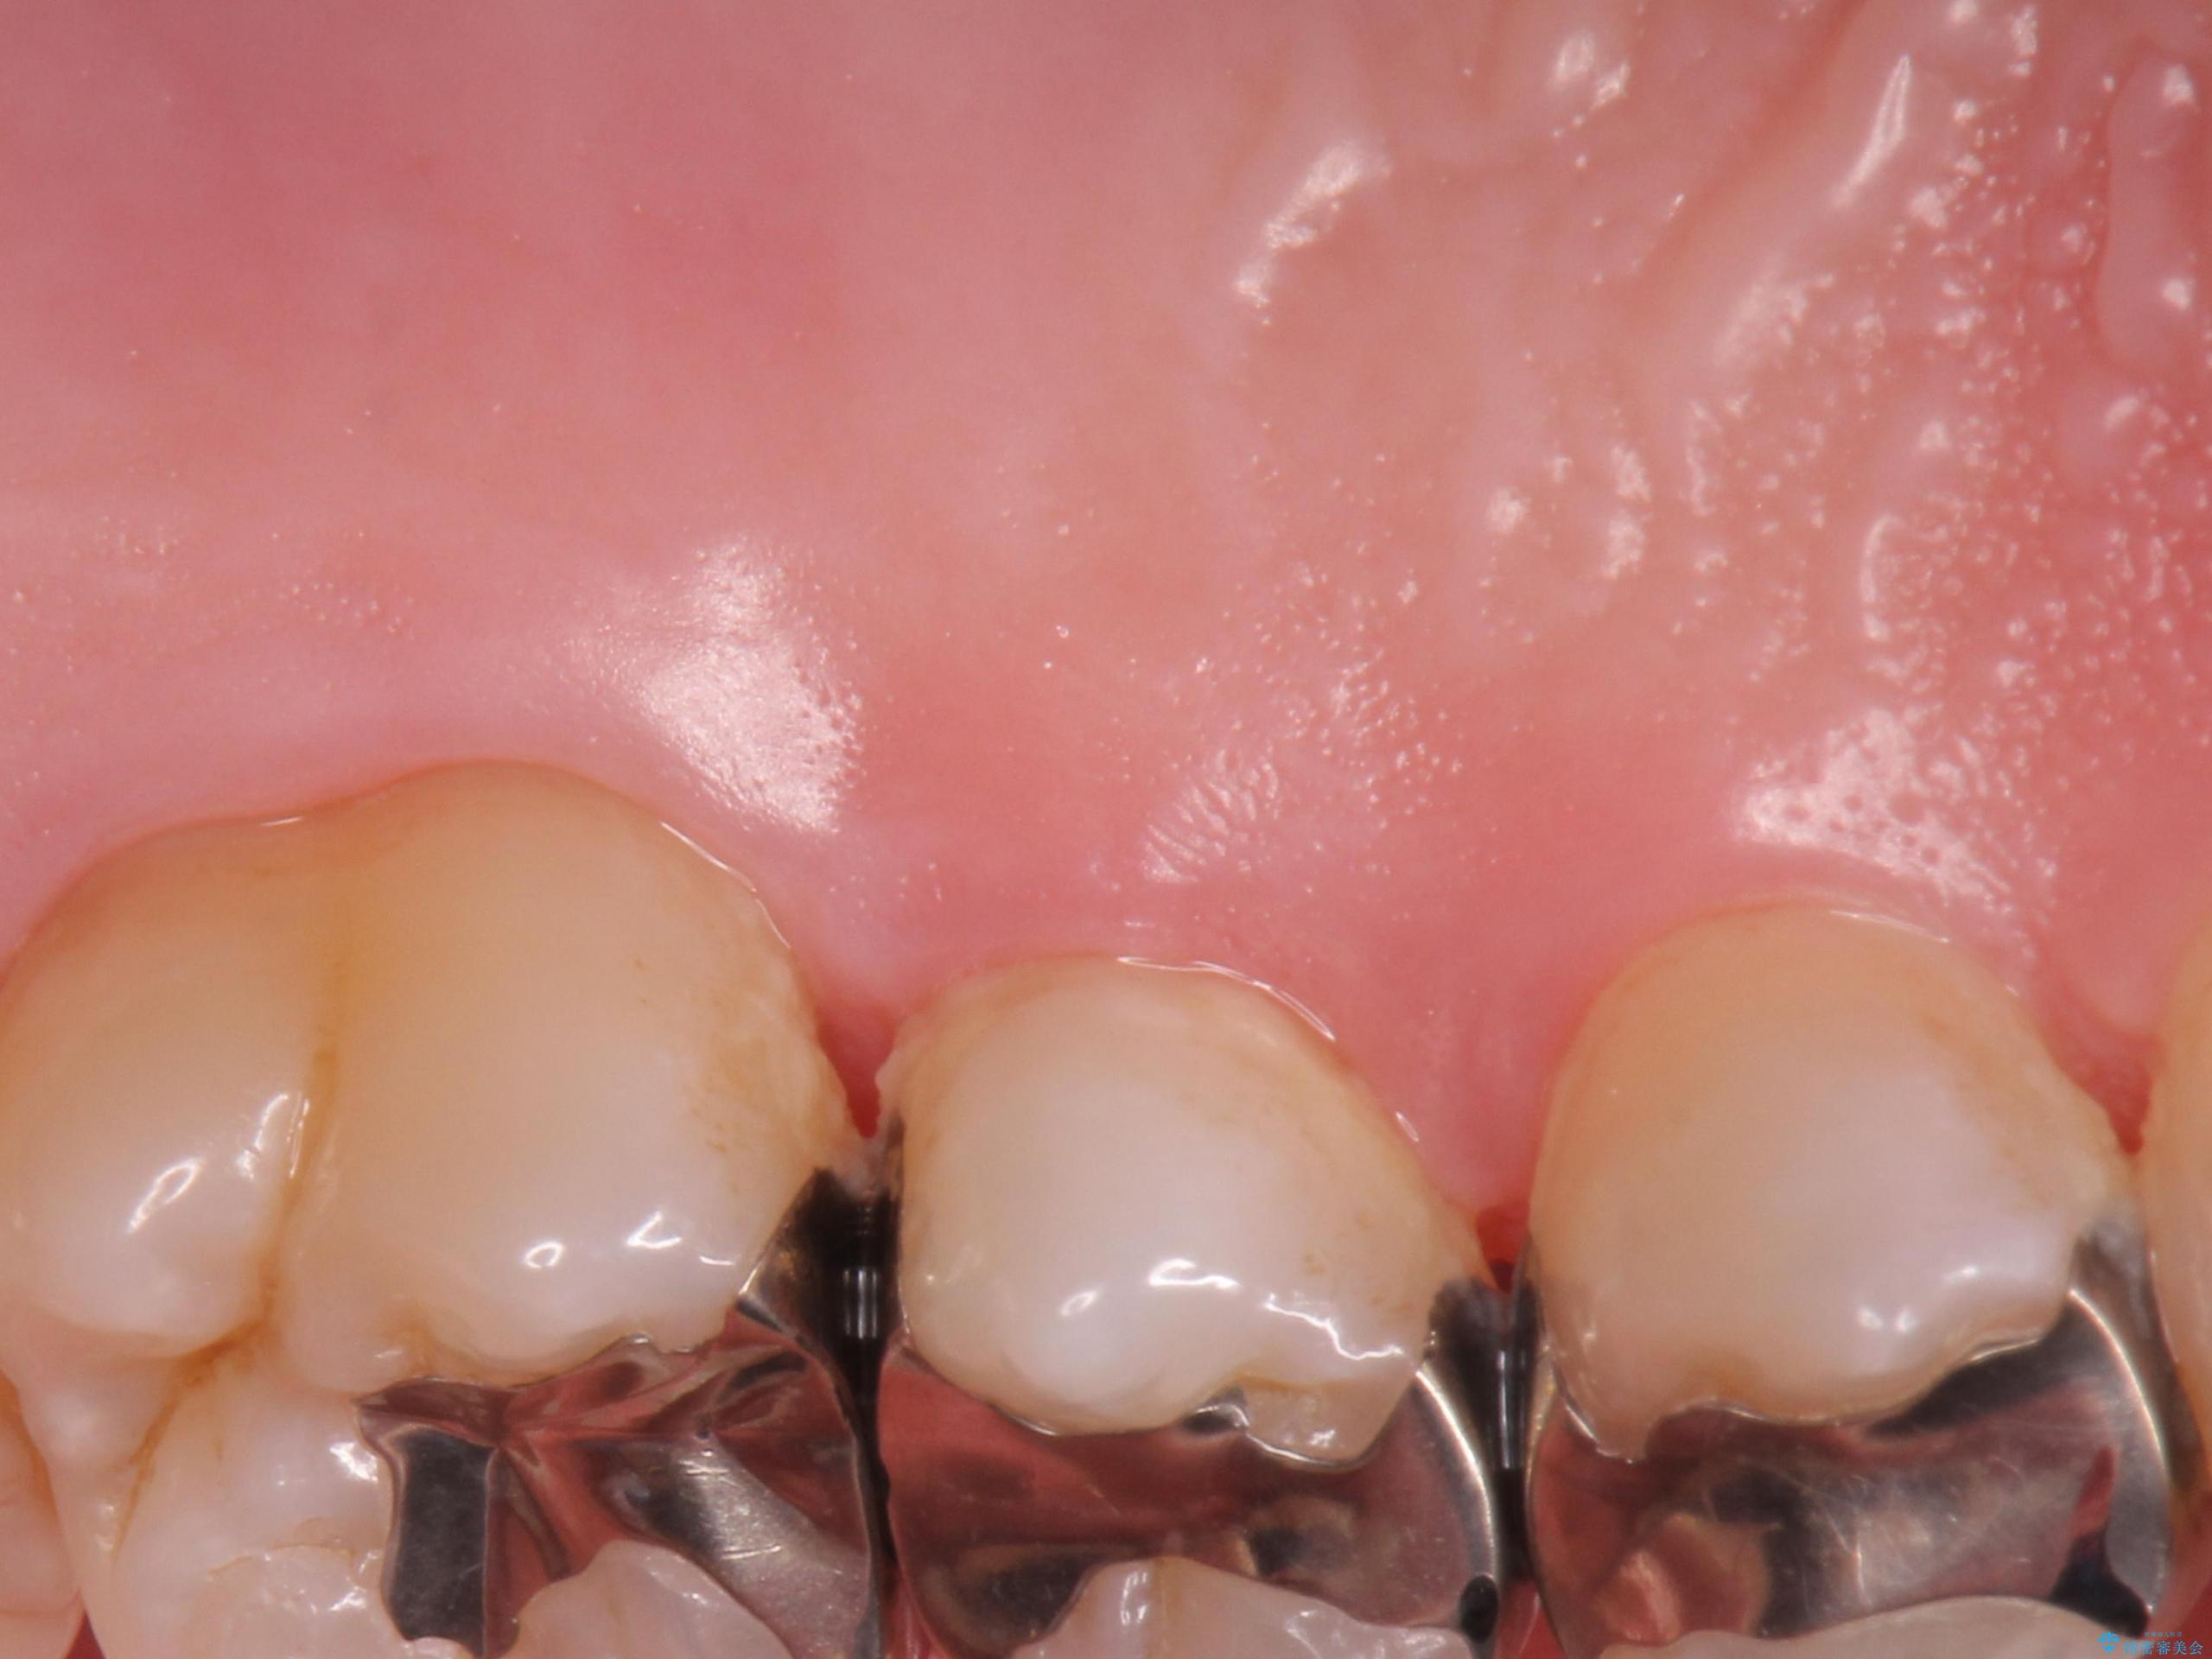

- 奥歯の歯茎が下がっていて(歯肉退縮)歯が染みるとのことで来院された患者様です。

退縮した歯茎に対して移植をすることで、しみる場所を覆う計画です。

歯根の分岐部よりも根尖側の頬側面が露出している状態でしたが、露出部位を分岐部までに抑えることができました。